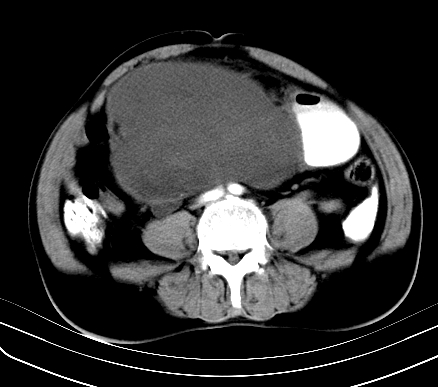

标题: CT19729B:男,74岁,因腿疼就诊,查体触腹部肿物,

增强扫描

静脉期

【ct表现】

1、肿块巨大,往往位于腹膜后,长大后才引起症状而就诊;那么位于腹膜后的肿瘤80%为恶性肿瘤。

2、实性肿瘤,增强扫描轻度不均强化,实性肿瘤一般不是好东西。

3、肿瘤边缘似见少许脂肪样密度。

4、腹膜后未见肿大淋巴结,但肿瘤于临近的肠管及组织接触紧密。

【诊断】

腹部占位,考虑位于腹膜后的恶性肿瘤,脂肪肉瘤(实体型)可能性大。

术后病理结果:腹膜后脂肪肉瘤。